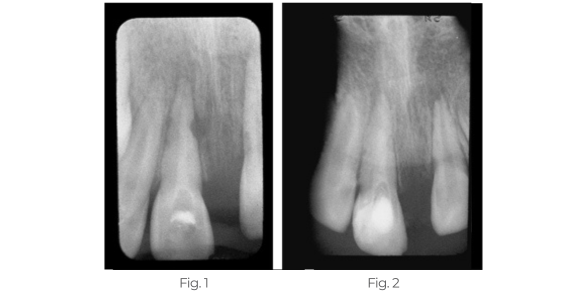

Bildung von Hartgewebe

Dieser Patient verlor seinen oberen linken zentralen Schneidezahn aufgrund einer traumatischen Verletzung.

Abb. 1: Die Röntgenaufnahme zeigt eine externe Wurzelresorption auf der mesialen Seite des oberen rechten mittleren Schneidezahns. Der Wurzelkanal wurde mit TempCanal gefüllt, um die Heilung zu fördern.

Abb. 2: Die 3 Monate später aufgenommene Röntgenaufnahme zeigt die Remineralisierung der mesialen Seite des Zahns.

Behandlung eines abgerissenen Zahns

Dieses Kind stellte sich mit avulsierten linken zentralen und traumatisierten rechten zentralen Schneidezähnen vor. Zwei Wochen nach der Replantation und Schienung wurde die Pulpa entfernt und Pulpdent® Paste in die Wurzelkanäle eingebracht. Der Fall wurde 12 Monate lang regelmäßig beobachtet und die Pulpdent Paste wurde bei jedem Besuch gewechselt. Nach einem Jahr wurden die Wurzelkanäle mit dem Pulpdent® Root Canal Sealer unter Verwendung der Pressure Syringe-Technik obturiert.

Abb. 1: Das Foto zeigt ein Kind mit einem avulsierten linken zentralen und einem traumatisierten rechten zentralen Schneidezahn.

Abb. 2: Die Röntgenaufnahme zwei Wochen nach der Replantation zeigt den replantierten Zahn, offene Wurzelspitzen und Knochenverlust. Bei diesem Besuch wurden die Wurzelkanäle ausgehandelt und Pulpdent Paste als Verband aufgetragen, um die Heilung zu stimulieren und einer traumatischen Abstoßung vorzubeugen (nicht abgebildet).

Abb. 3: Die Röntgenaufnahme ein Jahr nach der Behandlung zeigt Pulpdent Paste in den Wurzelkanälen, Apexifizierung und Knochenauffüllung.